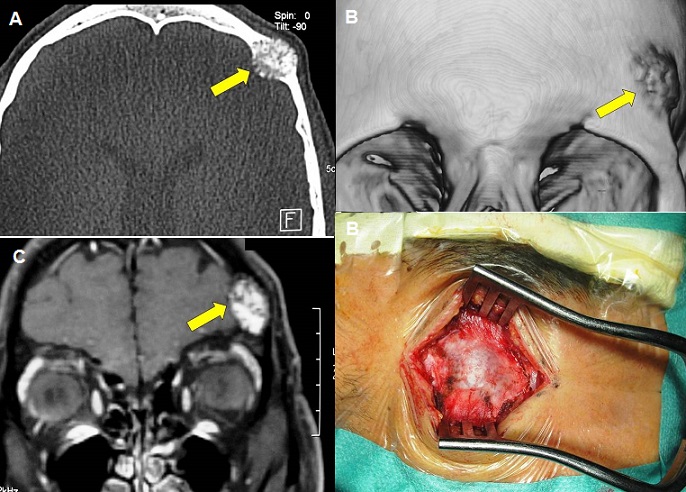

A 37-year-old previously healthy man presented with a localized headache and a progressive enlarging mass in the left frontal area for more than 8 months. He also reported a history of head injury in the same area sustained two years before. On physical examination, the mass (about 28 mm in diameter) was hard to pressure with freely mobile skin above the lesion in the left frontal sus-orbital region. Ophthalmologic and neurologic examinations were normal. Cranial computed tomography scan showed an osteolytic intradiploic lesion with poorly defined margins (A and B). Magnetic resonance imaging showed hyperintense lesion on T2-weighted image and hypointense on T1-weighted image with gadolinium enhancement (C). The lesion was extradural with slight brain mass effect. Surgery consisted of total resection of the bony bluish lesion (D) and cranioplasty. The postoperative course was uneventful. Histological study revealed a cavernous hemangioma of the diploe. Bone hemangioma is a vascular hemartoma: a benign tumor arising from the intrinsic vasculature of the bone, commonly seen in long bones and vertebrae. Skull cavernous hemangiomas are rare tumors for which the origin is not yet clear. We suspected that in our case head injury may have been the cause of cavernous hemangioma in the cranial vault.